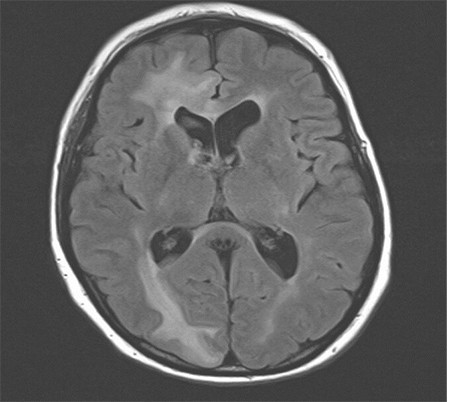

On magnetic resonance imaging (MRI) of the brain, progression of 2 areas concerning for recurrent disease versus radiation effect with mild surrounding edema in the right and left cerebellum was seen. The patient was treated with stereotactic radiosurgery (SRS), in which a follow-up MRI showed tumor regression. Most recent MRI brain showed increased enhancement and edema especially in the right frontal and right occipital regions (Figure 1).

Figure 1. Magnetic resonance imaging (MRI). Sagittal view of edematous lesions representing metastatic carcinoma in the right frontal and occipital regions